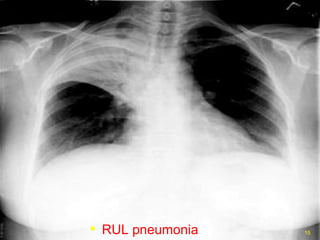

RUL pneumonia